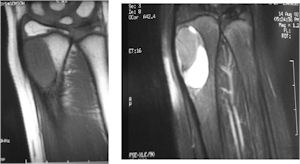

MRI:

- Also useful in determining extent

- There is often extensive edema around the tumor in the surrounding bone and soft tissues that can lead to a misdiagnosis of a malignant tumor.